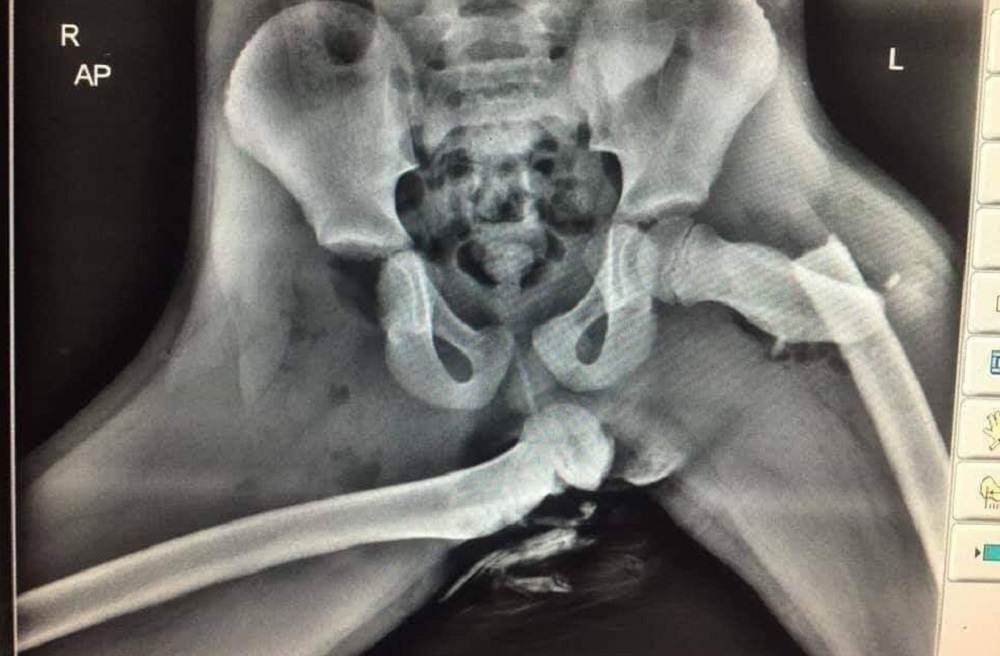

Nogi na desce w aucie + airbag? :)

@Dalmierz_Ploza buzię widzę w tej miednicy

@Dalmierz_Ploza uderzenie z prawej strony na wysokości prawego stawu biodrowego. Siła skierowana poziomo.

Wypadek z pieszym?

Ktoś jeszcze długo na kibelku nie posiedzi.